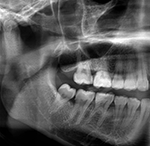

Which examinations may be considered in an individual case depends on the procedural situation and the legal basis. Typical components are the physical examination, the dental examination including orthopantomogram, the radiological assessment of the hand, and, in cases of advanced maturity and a corresponding question, supplementary findings at the clavicle. What is decisive is the ordered overall appraisal; an isolated single finding does not carry the conclusion. The evidential value therefore does not arise from a single image or a single maturity feature, but from the methodologically grounded combination of the permissible findings.